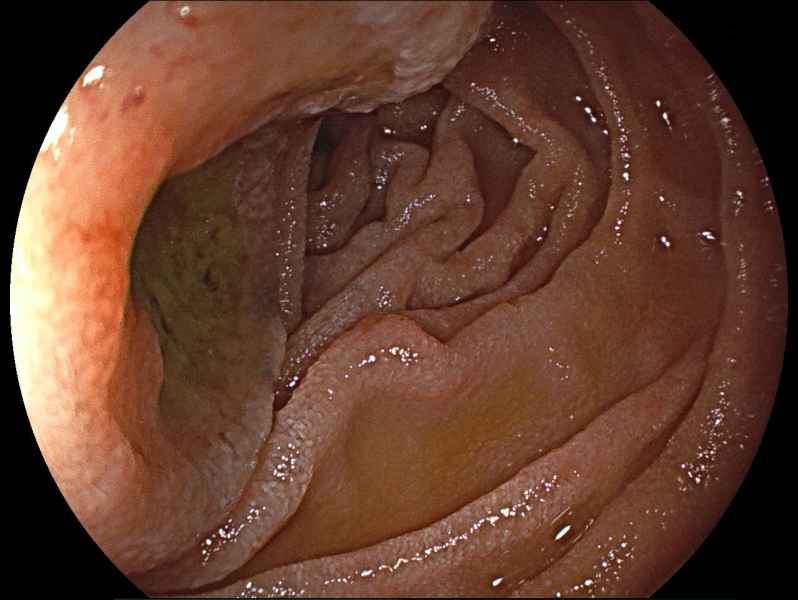

Gastric Crohn's disease